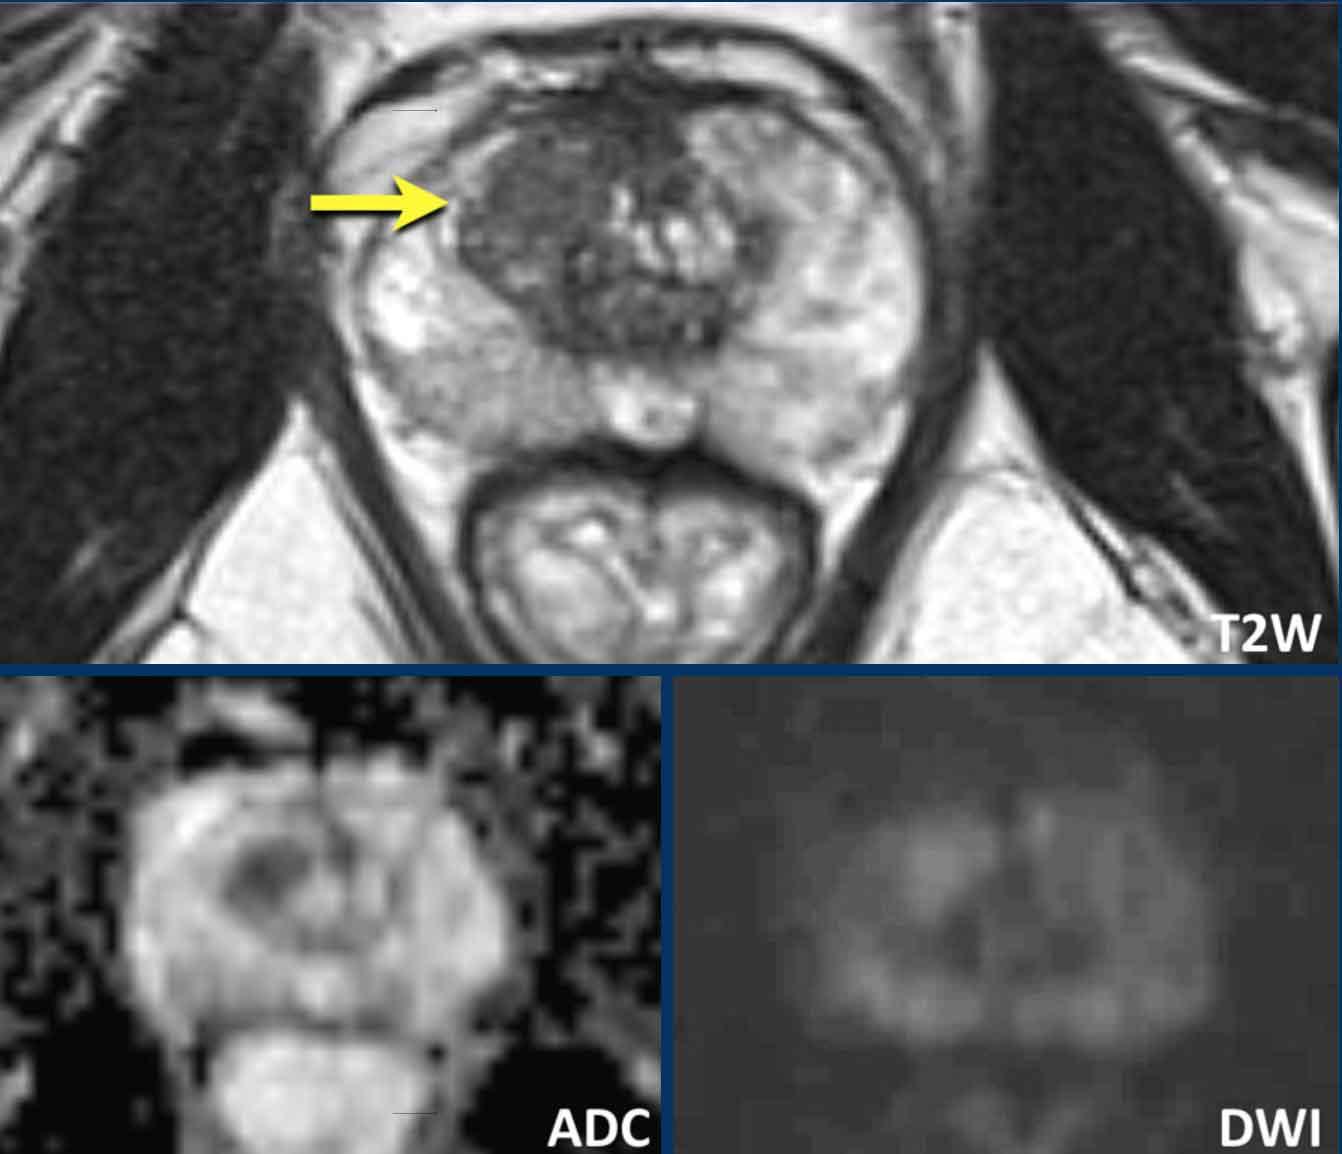

Hãy quan sát hình ảnh trước rồi tiếp tục đọc.

Các phát hiện bao gồm:

- Một tổn thương phân loại đánh giá PI-RADS 4 nằm ở vùng ngoại vi bên trái của phần giữa tuyến tiền liệt.

Giảm tín hiệu rõ rệt khu trú trên ADC (mũi tên vàng) (điểm 4), tương ứng với vùng giảm tín hiệu trên chuỗi xung T2W (điểm 4).

Điểm Gleason của tổn thương này là 3+4.

- Một tổn thương phân loại đánh giá PI-RADS 3 nằm ở vùng ngoại vi bên phải, với giảm tín hiệu khu trú nhẹ trên ADC (mũi tên xanh lá) và đồng tín hiệu trên DWI (điểm 3).

Không thực hiện DCE và không thể phân biệt thêm được.

Sinh thiết không cho thấy bất kỳ dấu hiệu ác tính nào.